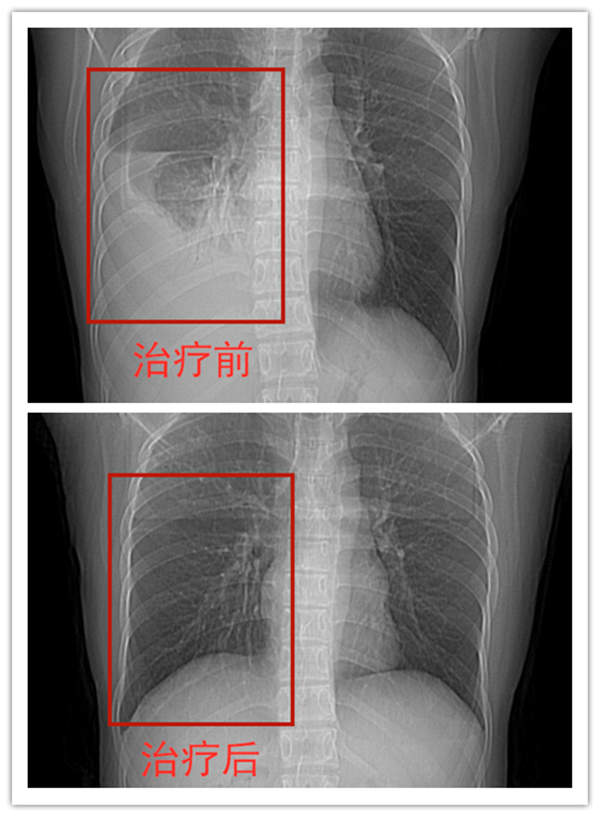

一个月前,新冠肺炎特殊的疫情,王先生因复工需要体检,就在户口所在地拍片,无意间被医生发现了胸腔积液,就建议他来南阳市第六人民医院做进一步检查,医生看了胸部CT,直接让他住院治疗,这可让王先生吓了一跳,他并没有感觉到像以前患病时的胸闷不适、咳嗽,只是偶尔出现活动后气急,这几年来,也没再做过任何检查,偶尔加重了便以为是感冒或者抽烟、年龄增加等原因,就自行在附近药店买些口服百喘朋及平喘止咳糖浆等治疗,怎么也没想到再次复发。带着诸多疑惑,王先生再次来到南阳市第六人民医院。

经过牛主任的详尽介绍,王先生对自己这次发病的原因终于明白了,原来是因为在没有完成疗程前就自行停药而引起的复发!所幸的是他的脓液经过几次的抽吸治疗后已大大减少,近日就可出院。可见,肺结核患者是不能轻易停药,如果盲目停药,病情有复发的可能,更会影响治疗的效果,浪费前边的治疗。他表示,这次一定会按照医生的要求正规治疗,遵从医嘱,按时吃药,切不可拿自己的生命和健康开玩笑!